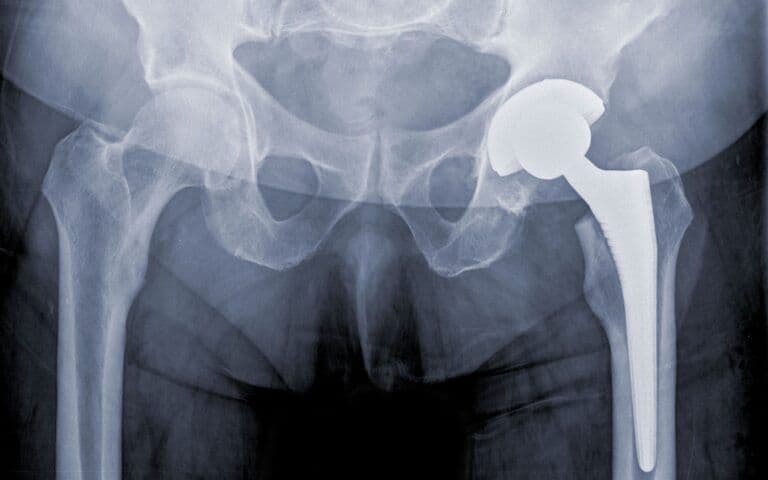

There are two main types of hip replacement surgery: total hip replacement (THR) and partial hip replacement. In a total hip replacement, both the acetabulum (the hip socket) and the femoral head (the ball of the thigh bone) are replaced. In a partial hip replacement, only the femoral head is replaced. The choice between these procedures depends on the patient's specific condition and the extent of joint damage.

Total hip replacement (THR), on the other hand, involves replacing both the femoral head and the acetabulum with prosthetic components. This comprehensive approach is often necessary for individuals suffering from severe osteoarthritis, rheumatoid arthritis, or other degenerative conditions that affect both parts of the hip joint. During a total hip replacement, the surgeon removes the damaged cartilage and bone from both the femoral head and the acetabulum, replacing them with artificial components made of metal, ceramic, or plastic. The prosthetic components are designed to mimic the natural movement of the hip joint, providing significant pain relief and improved mobility.

Total hip replacement surgery involves the use of various materials to create prosthetic components that replace the damaged parts of the hip joint. These materials are carefully selected for their durability, biocompatibility, and ability to replicate the natural movement of the hip. The primary components of a total hip replacement include the femoral stem, femoral head, acetabular cup, and a liner that fits within the acetabular cup.

The femoral stem, which is implanted into the thigh bone (femur), is typically made of metal alloys such as titanium or cobalt-chromium. Titanium is favored for its lightweight nature, strength, and excellent biocompatibility, allowing it to integrate well with the surrounding bone. Cobalt-chromium alloys are known for their high wear resistance and strength, making them suitable for the demanding environment of the hip joint.

The femoral head, which replaces the ball of the thigh bone, can be made of either metal or ceramic. Ceramic femoral heads are becoming increasingly popular due to their smooth surface, which reduces friction and wear against the acetabular cup. Metal femoral heads, often made of cobalt-chromium, are also commonly used for their durability and wear resistance.

The acetabular cup, which replaces the hip socket, is usually made of metal alloys such as titanium or cobalt-chromium. To reduce wear and provide a smooth articulation surface, the acetabular cup is often lined with a polyethylene (plastic) liner or a ceramic liner. Highly cross-linked polyethylene liners have improved wear resistance compared to traditional polyethylene, making them a popular choice for hip replacements.